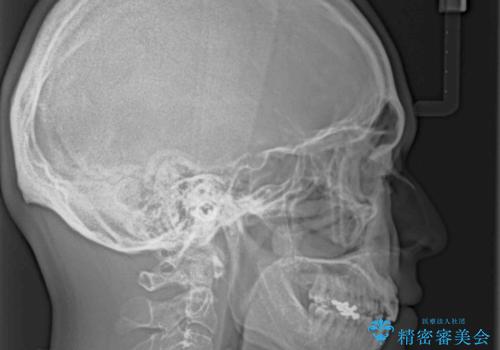

しゃくれて口が閉じられない ワイヤー装置での抜歯矯正

- 口がうまく閉じられないとのことで来院された患者様です。

上下唇をしっかり合わせようとすると、顎先が前方に突出してしまうほど口が閉じにくい状態でした。

口元の突出感を改善するために上下左右の第一小臼歯4本を抜歯し、ワイヤー装置にて矯正治療を行うこととしました。

また、上下前歯は舌の突出癖による開咬となっていたため、舌のトレーニングを徹底するよう指示しました。